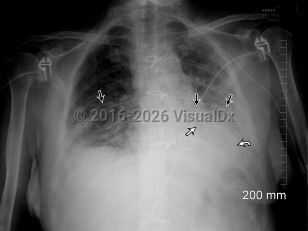

Fever, Cough, 50-59 year old Female

COVID-19

Community-acquired pneumonia

Viral pneumonia